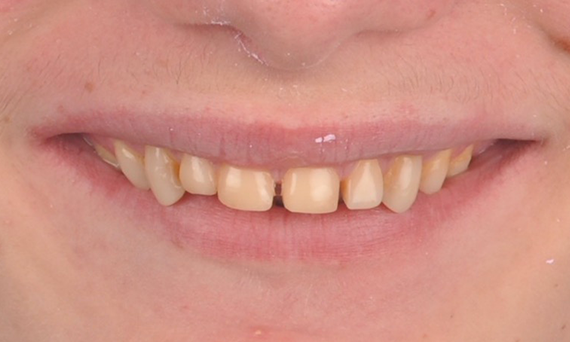

Amelogenesis Imperfecta

Full mouth rehabilitation with 28 all-ceramic restorations

A particular and protracted case of skeletal Class II malocclusion and generalized amelogenesis imperfecta in a teenager was referred for prosthetic rehabilitation. The aim of the treatment was to prepare the remaining tooth structure, remove undercuts, and make room for all-ceramic crowns covering the entire dentine and simulating the lost enamel.

Before: Initial situation prior to orthodontic treatment.

After: Final result, 1 week post-operative.

Alexander Declerck, (DDS, MSc)

Sint-Martens-Latem, Belgium